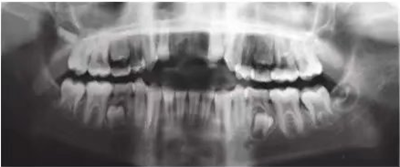

車禍后,一名10歲男孩被送往Shariati醫(yī)院急診科。診斷出上頜中切牙的脫落和側(cè)切牙的嵌入(圖1)。脫落的中切牙丟失了,沒(méi)有進(jìn)行再植。全景片示除第二磨牙外的恒牙列(圖2)。

圖2. 初診全景片